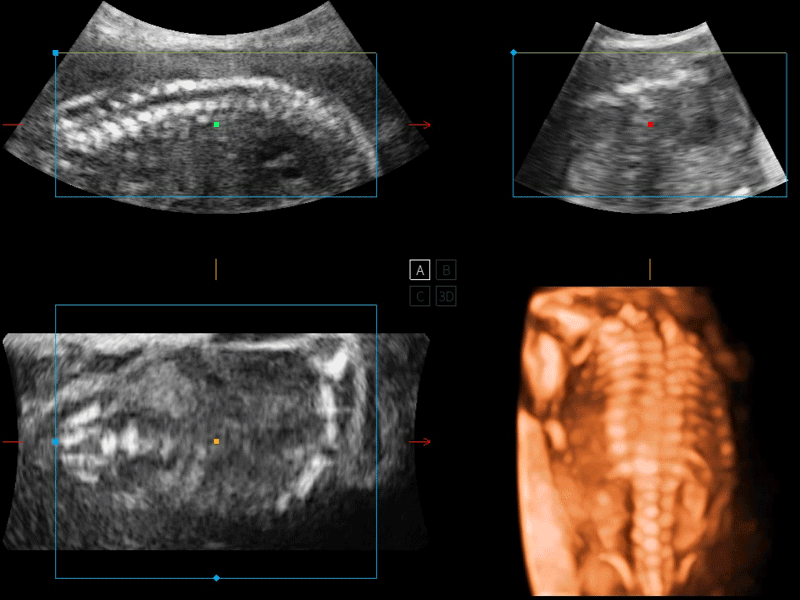

S-Live 高分辨率容积成像

通过仿真成像技术对3D/4D立体数据进行渲染,多种初始光源位置可选,并支持轨迹球360°光源位置自由调节,清晰显示不同方位容积图像细节。

临床图像